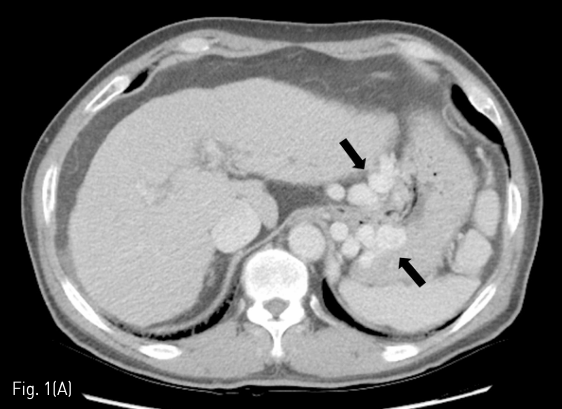

Fig 2A

(A) After vascular plug (white arrow) placement in narrowest portion of the gastro-renal shunt via left inferior phrenic vein, additional embolization of the gastro-renal shunt, gastric varices, and afferent vein (arrow heads) was performed using gelatin sponges through the 4-F catheter (black arrow).